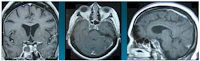

Non-Functioning Pituitary Macroadenoma Thinesh Kumran1,2, Saffari Haspani1,2, Jafri malin abdullaH1,4, Azmi alias1,2, Figure 1: MRI image of Pituitary Gland (Saggital View), shows method of Pituitay Stalk Angle measuremen. 74 www.mjms.usm.my ... Access Doc